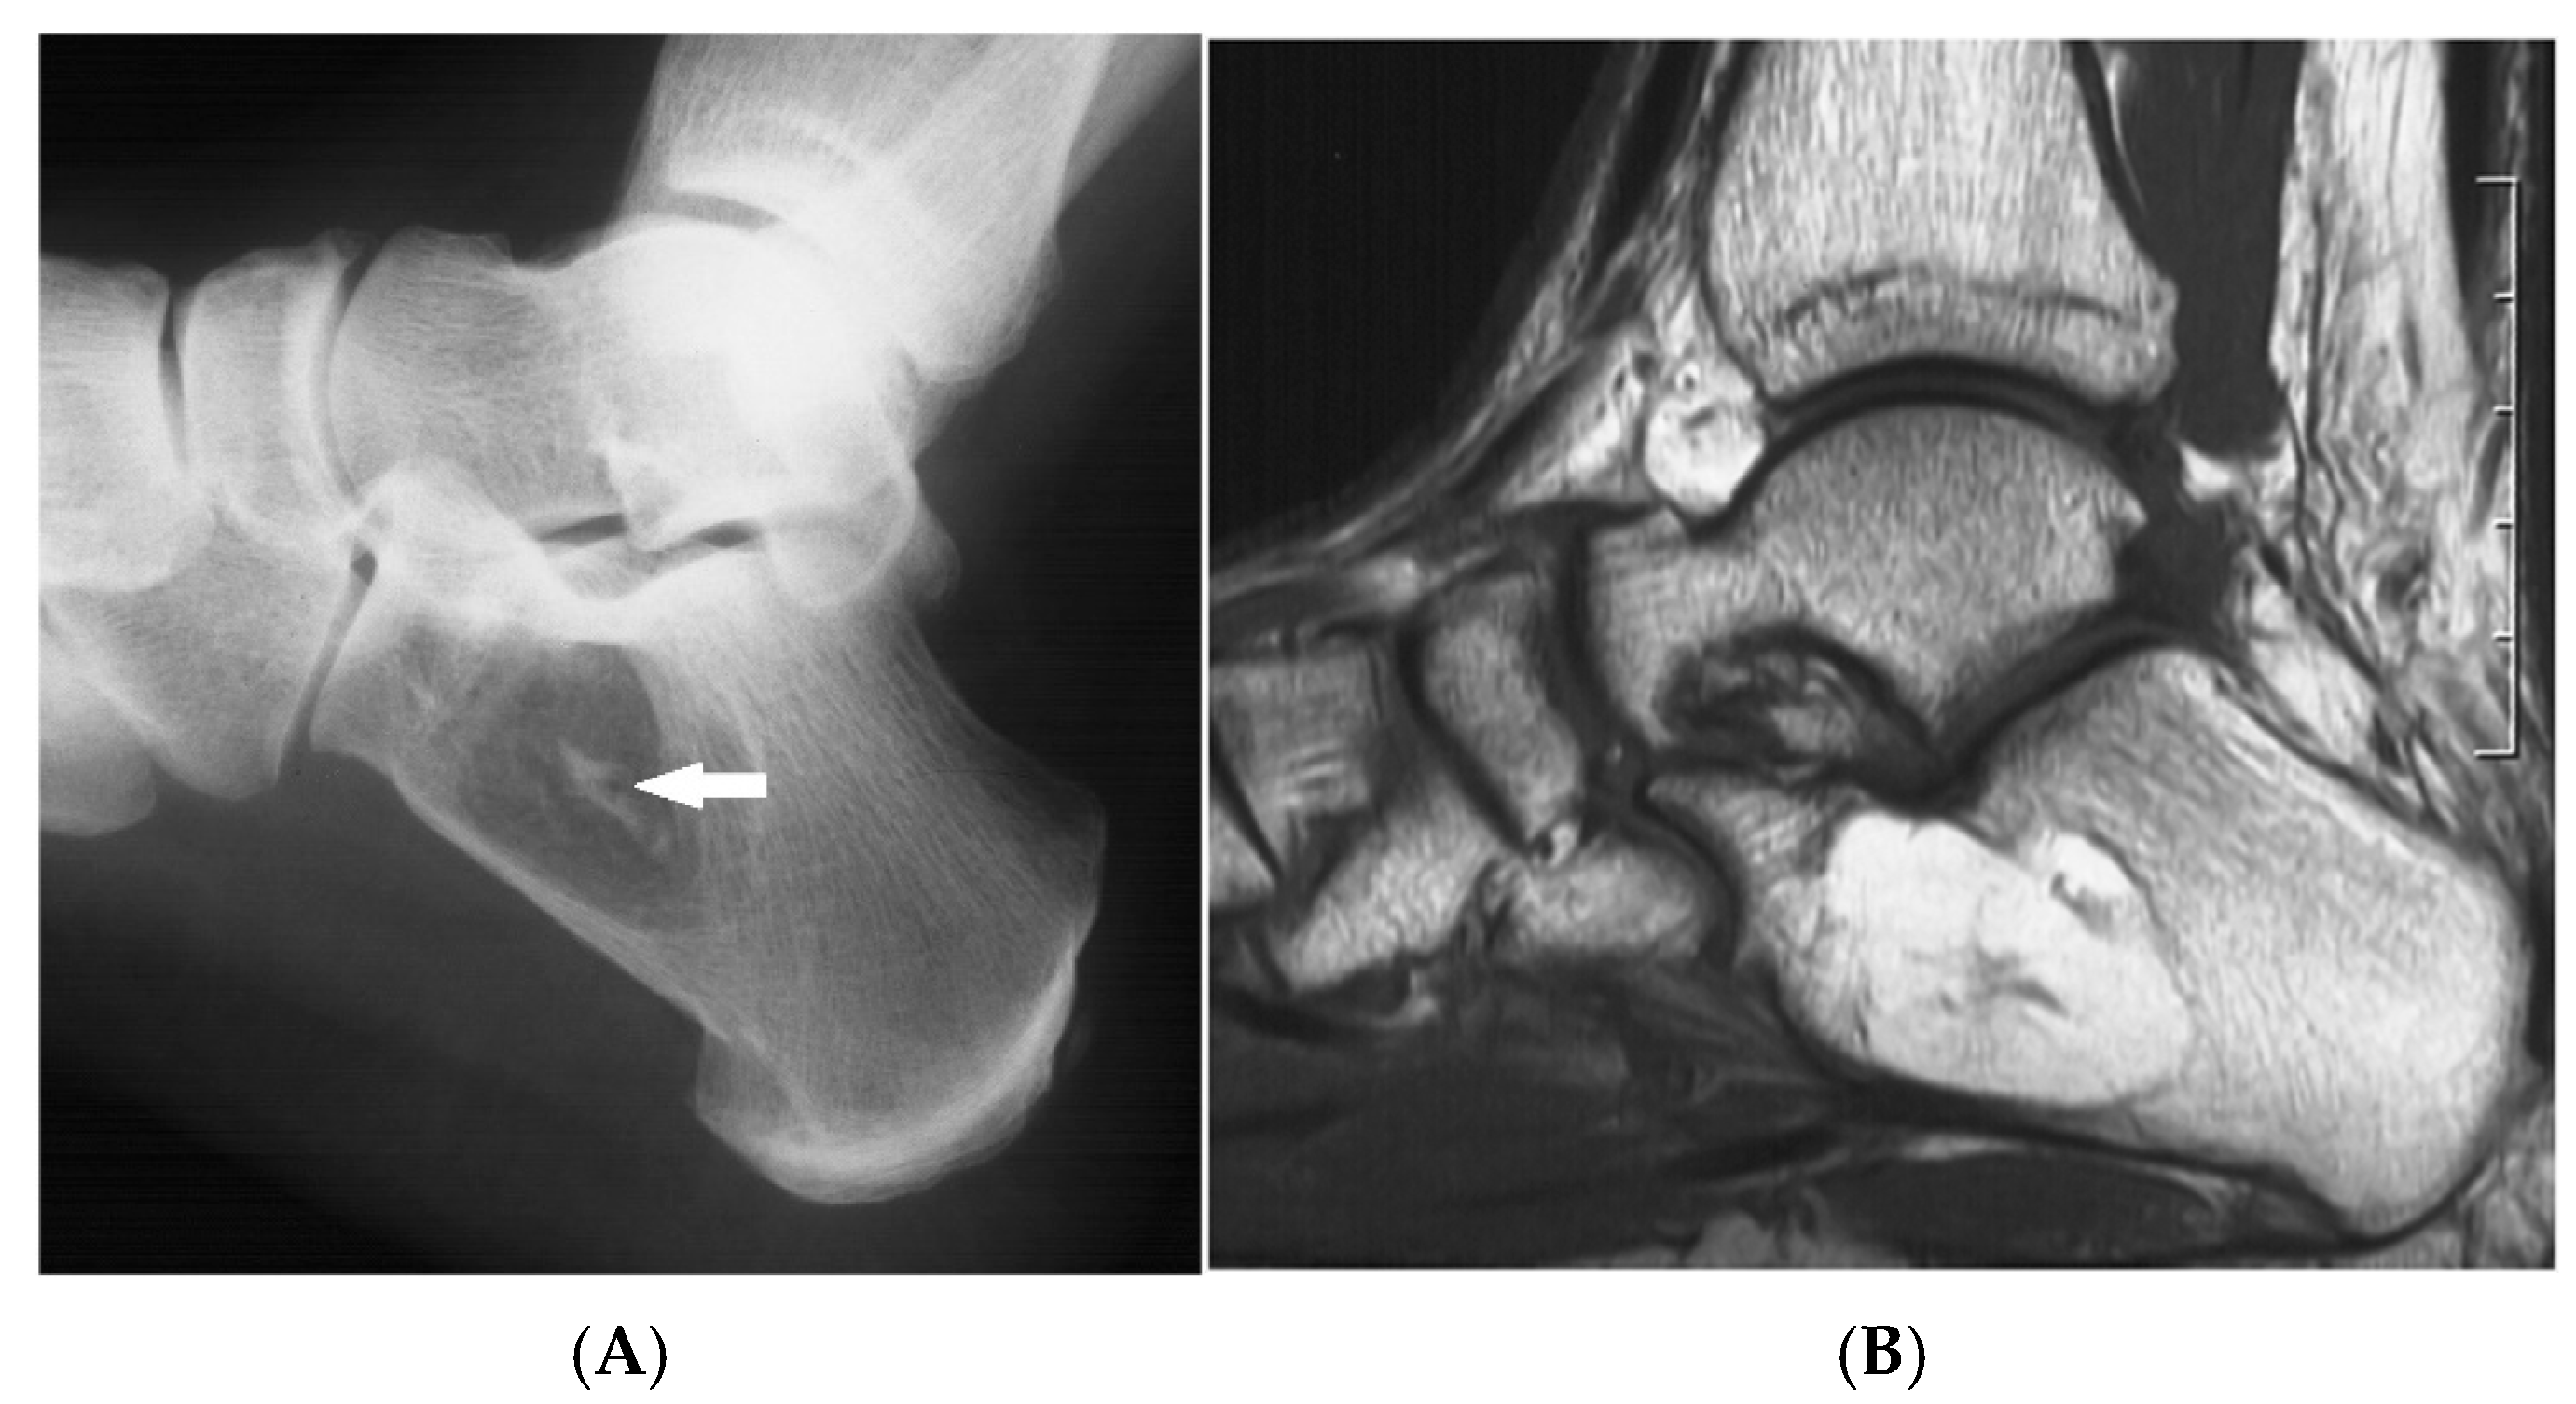

Figure 3.

Intraosseous lipoma, calcaneum. (A) Plain radiograph demonstrating the classic location of the lesion with “bull’s eye” sign (solid white arrow). (B) Sagittal T1W MRI with fat-containing lesion.